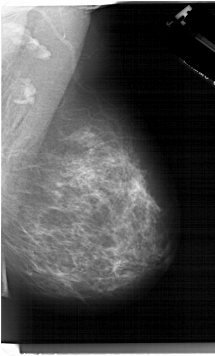

A_1284_1.LEFT_MLO

LEFT_MLO LINES 6616 PIXELS_PER_LINE 4096 BITS_PER_PIXEL 12 RESOLUTION 43.5 OVERLAY